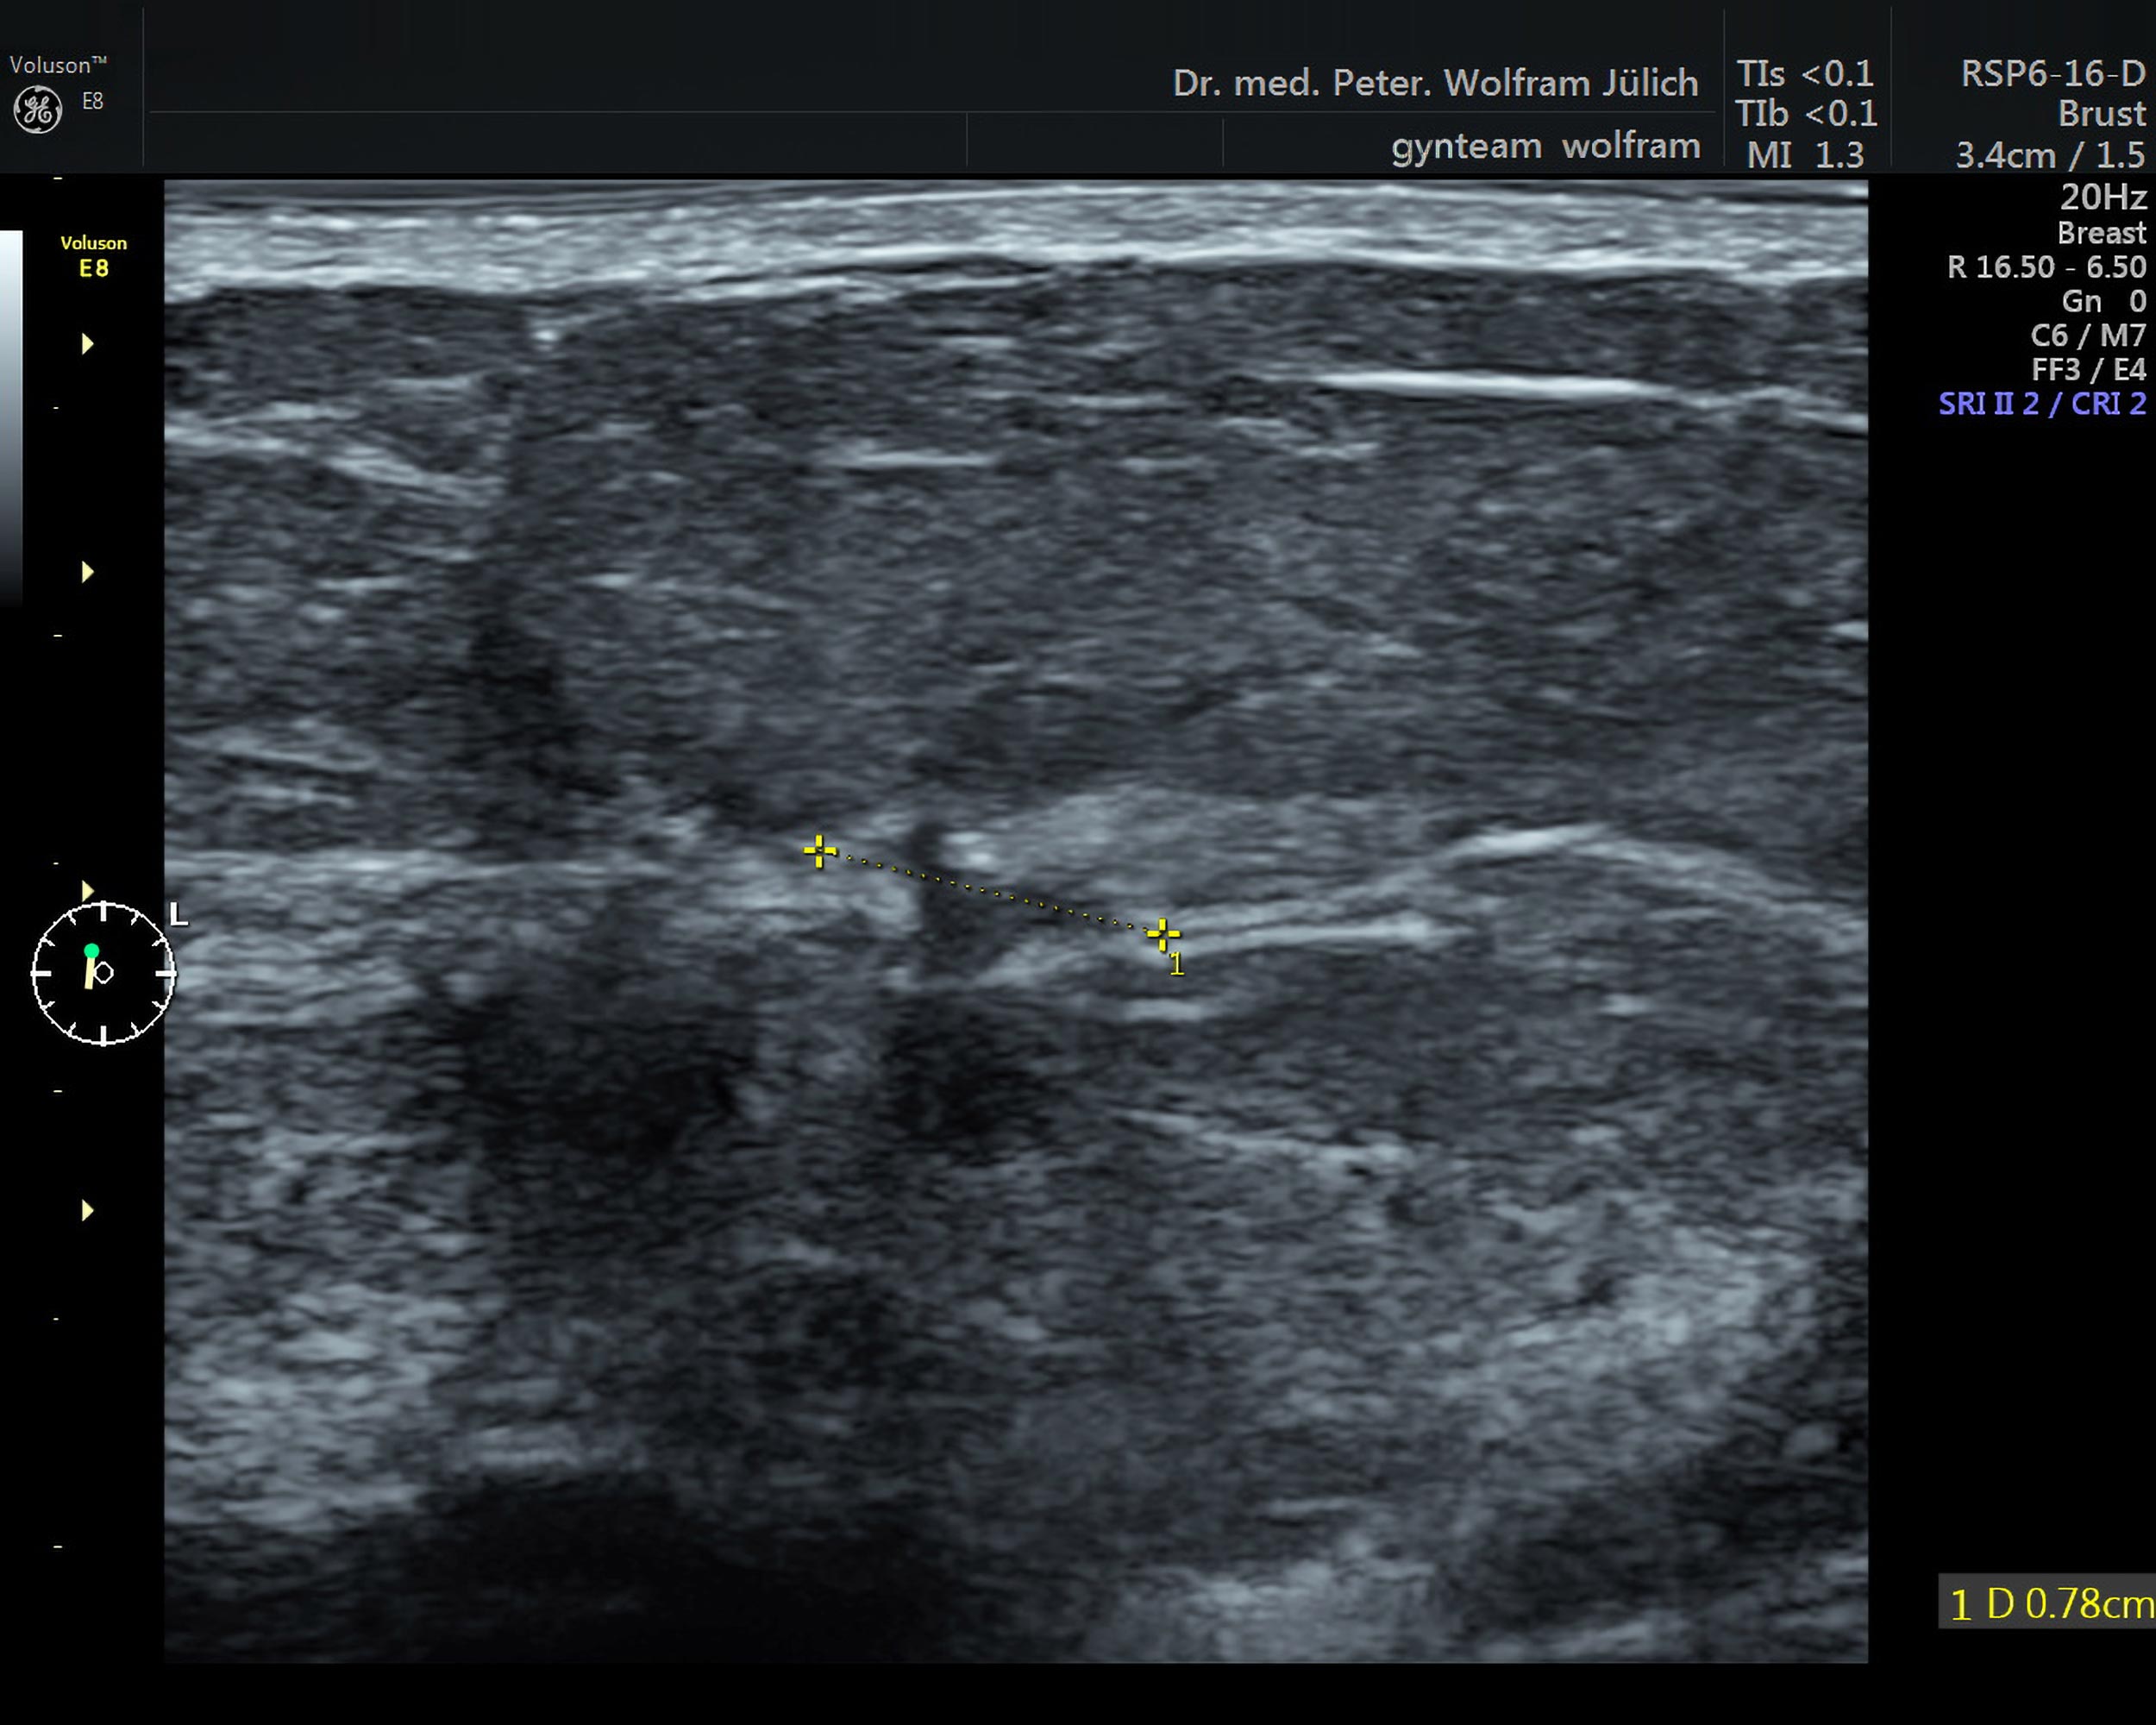

Die Ultraschalltechnologie hat sich in den vergangenen Jahren rasant weiterentwickelt. Die Detailauflösung der neuesten Geräte hat sich in den letzten drei Jahrzehnten in etwa verdreifacht.

In unseren Praxisräumen nutzen wir ein hochmodernes Ultraschallgerät der neuesten Generation der Voluson-Serie. Es bietet neben einem ultrahochauflösenden Schallkopf  folgende zusätzliche Techniken an::

Die Tastuntersuchung der Brust ist angesichts der heute zur Verfügung stehenden bildgebenden Verfahren zu ungenau: Ein Tumor hat zum Zeitpunkt der Tastbarkeit meist schon eine Größe von 2cm und darüber- das erfüllt nicht den Anspruch der Früherkennung. Mit modernen Ultraschallgerätengeräten lassen sich Tumore bereits ab 2mm darstellen.